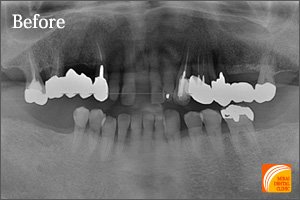

症例1

Before

期間 :11カ月

回数 :6回

費用 :1,274,400円

内容 :インプラント3本、GBR,外科用ステント、セラミック冠3本分含む

After

上の前歯2本を不慮の事故で抜歯せざるをえなかった患者さんです。 人工骨を足してインプラント2本を埋入することにより本物の歯と同じような歯が出来あがりました。